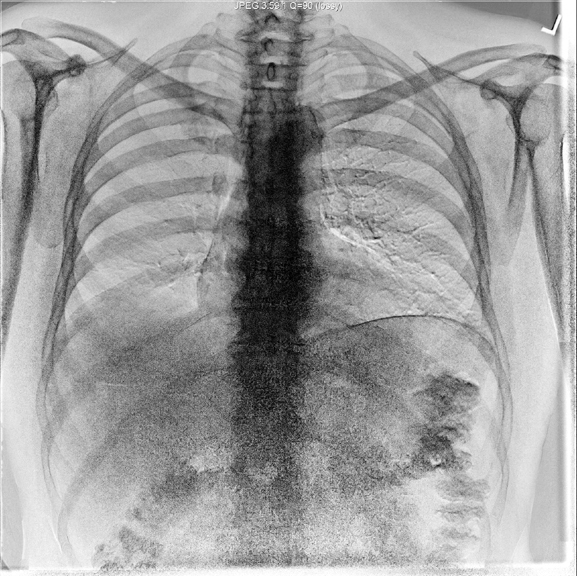

Identify the anterior and posterior ribs. Click the image for labeling.